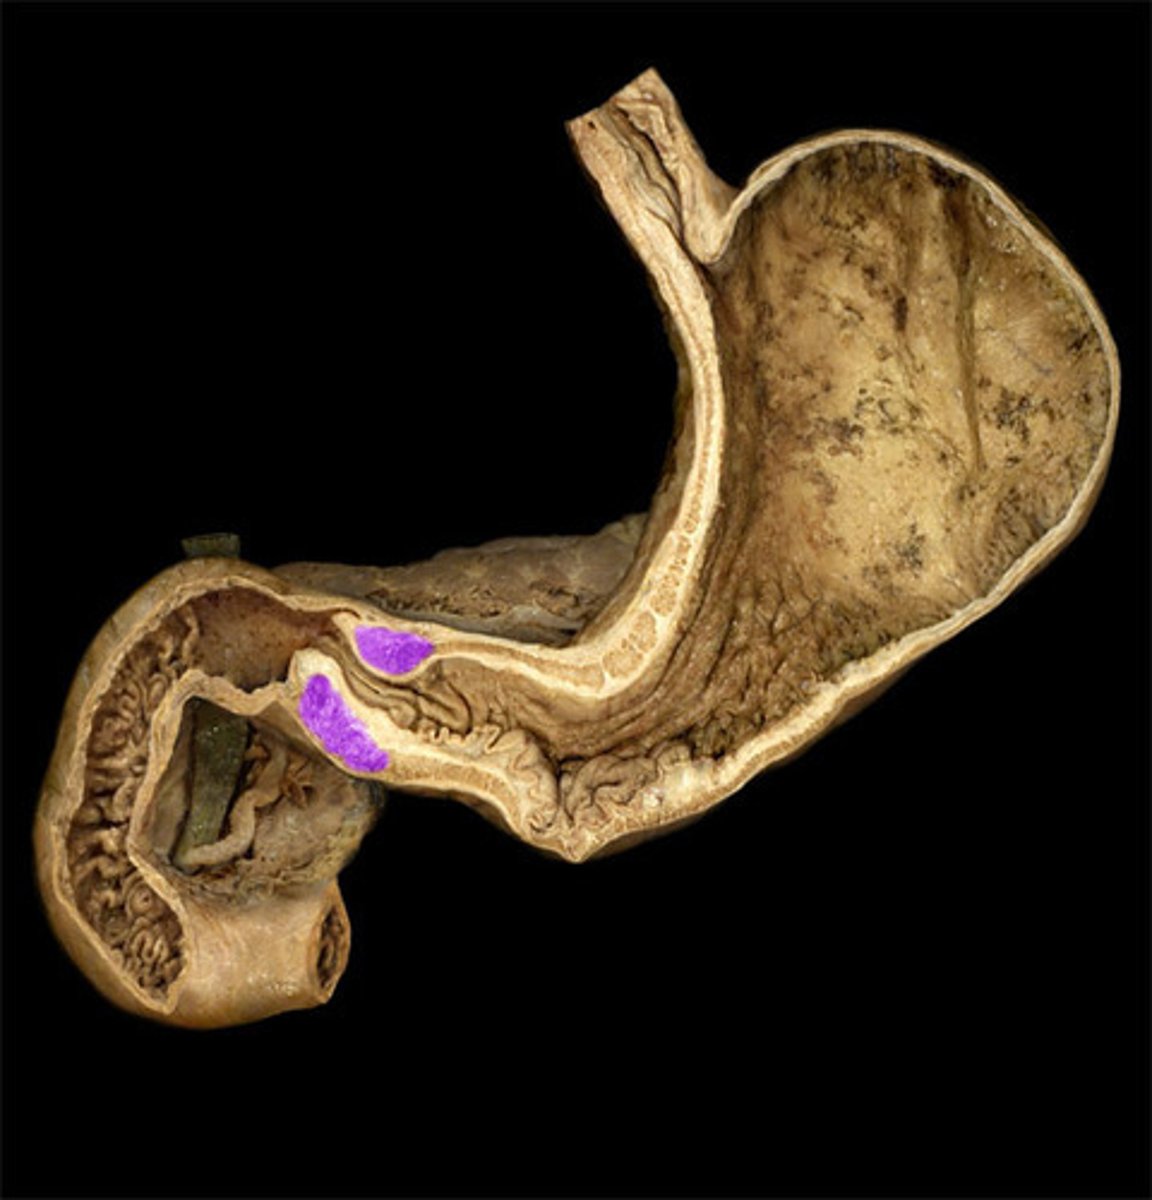

Cardia

Pylorus

Pyloric Sphincter

Gastric Rugae

Duodenum

Head (of Pancreas)